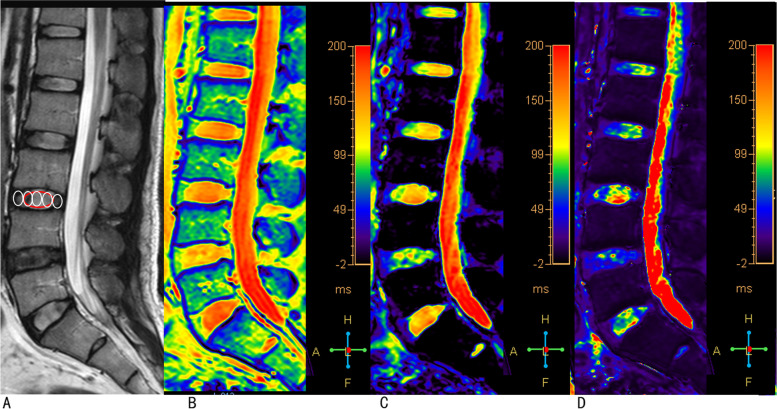

The raw data of T1ρ mapping were fitted on a pixel-by-pixel basis to the exponentially decaying T1ρ function using IDL 6.3 (ITT Visual Information Solutions, Boulder, CO) to generate a T1ρ map, and the T2 and T2* maps were generated and analyzed by using Image J software (National Institutes of Health, Bethesda, MD). Regions of interest (ROIs) were manually placed on the NP, anterior annulus fibrosus (AAF) and PAF of the T1ρ, T2, and T2* maps (Fig. 1). The anterior and posterior 20% of the disk diameter were labeled as AF with the remaining central 60% representing the NP [23, 28]. Values of AAF and PAF were averaged as the value for the AF. All the ROI measurements were performed twice by an observer with an interval of one month.

Fig. 1.

Representative images of sagittal T2-weighted images, T1ρ map, T2 map and T2* map. Five oval regions-of-interest (ROIs) were firstly placed on the T2-weighted images (A), then the ROIs were transferred to the T1ρ map (B), T2 map (C), and T2* map (D). The central three ovals (included in one red oval) represent nucleus pulposus, and the ventral and dorsal one represents anterior annulus fibrosus and posterior annulus fibrosus, respectively